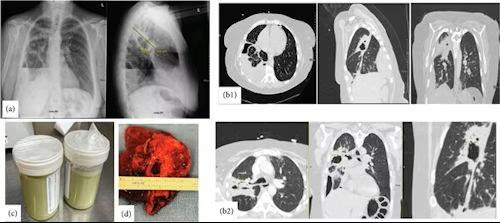

Фото 1: (а) Первичная рентгенография грудной клетки при поступлении показывает обширное гетерогенное помутнение правого легкого, которое, по-видимому, представляет собой толстостенное полостное образование размером около 4,8 × 10,5 см. Умеренный правосторонний гидропневмоторакс у основания легкого с сопутствующим уровнем жидкости и воздуха, что указывает на эмпиему. (b) b1: Утолщение или повреждение полости с толстыми стенками в задней правой верхней доле. Имеется сложный умеренный выпот в правой плевре с содержанием воздуха и жидкости, что указывает на эмпиему. В правом легком имеется обширное парабронхиальное утолщение. b2: Компьютерная томография грудной клетки после введения трубки; желтый маркер указывает на бронхолегочный свищ, который был причиной постоянной утечки воздуха. (c) Гной после введения грудной трубки. (d) Абсцесс правой верхней доли после лобэктомии.